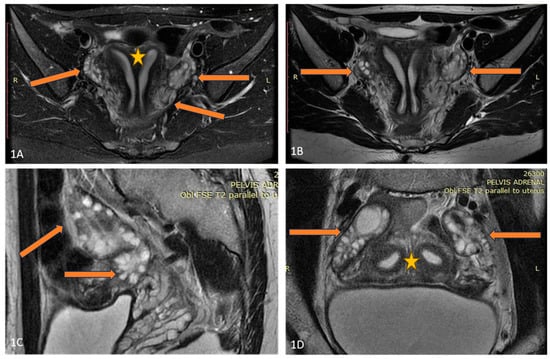

A 25-year-old lean Caucasian woman (BMI 19.0 kg/m2) was referred to the Endocrine Department because of hirsutism. After menarche at the age of 16 years, she had suffered from oligomenorrhea. Oral contraceptive treatment had been provided, but stopped because of the development of breast fibroadenoma. However, over the last three years, the menstrual pattern has become regular. She complained of slightly increased non-progressive hair growth on androgen-dependent zones since puberty, which was treated locally by a dermatologist. Polycystic ovary syndrome was suspected, based on her complaints (Table 1). Laboratory results showed upper-normal testosterone and increased levels of 17-OH progesterone. Therefore, congenital adrenal hyperplasia was excluded through a short Synacthen test. The blood count, blood glucose, lipid panel, and routine biochemical parameters, as well as thyroid function, were normal, while the AMH was significantly increased (23 ng/mL). A pelvic ultrasound revealed uterus didelphys with two separated cervices and a septated distal vagina. The ovaries were significantly increased in volume (“double ovaries”) but without pathological findings. The subsequent magnetic resonance imaging (MRI) (Figure 1) confirmed the ultrasound description. No tumor was found in the ovaries, and the investigated tumor markers (CEA, hCG, alpha-fetoprotein, LDH, and Ca-125) were in the reference ranges.

Figure 1. (AD) Axial T2FSE Fat Sat and T2FSE images (A,B) of the patient demonstrate uterus didelphys (orange star) and double bilateral ovaries (arrows). A sagittal T2 FSE image (C) shows double, partially fused ovaries. Two separate uterine cavities and bilateral ovaries are seen in the paracoronal oblique plane, parallel to the uterine axis (D).